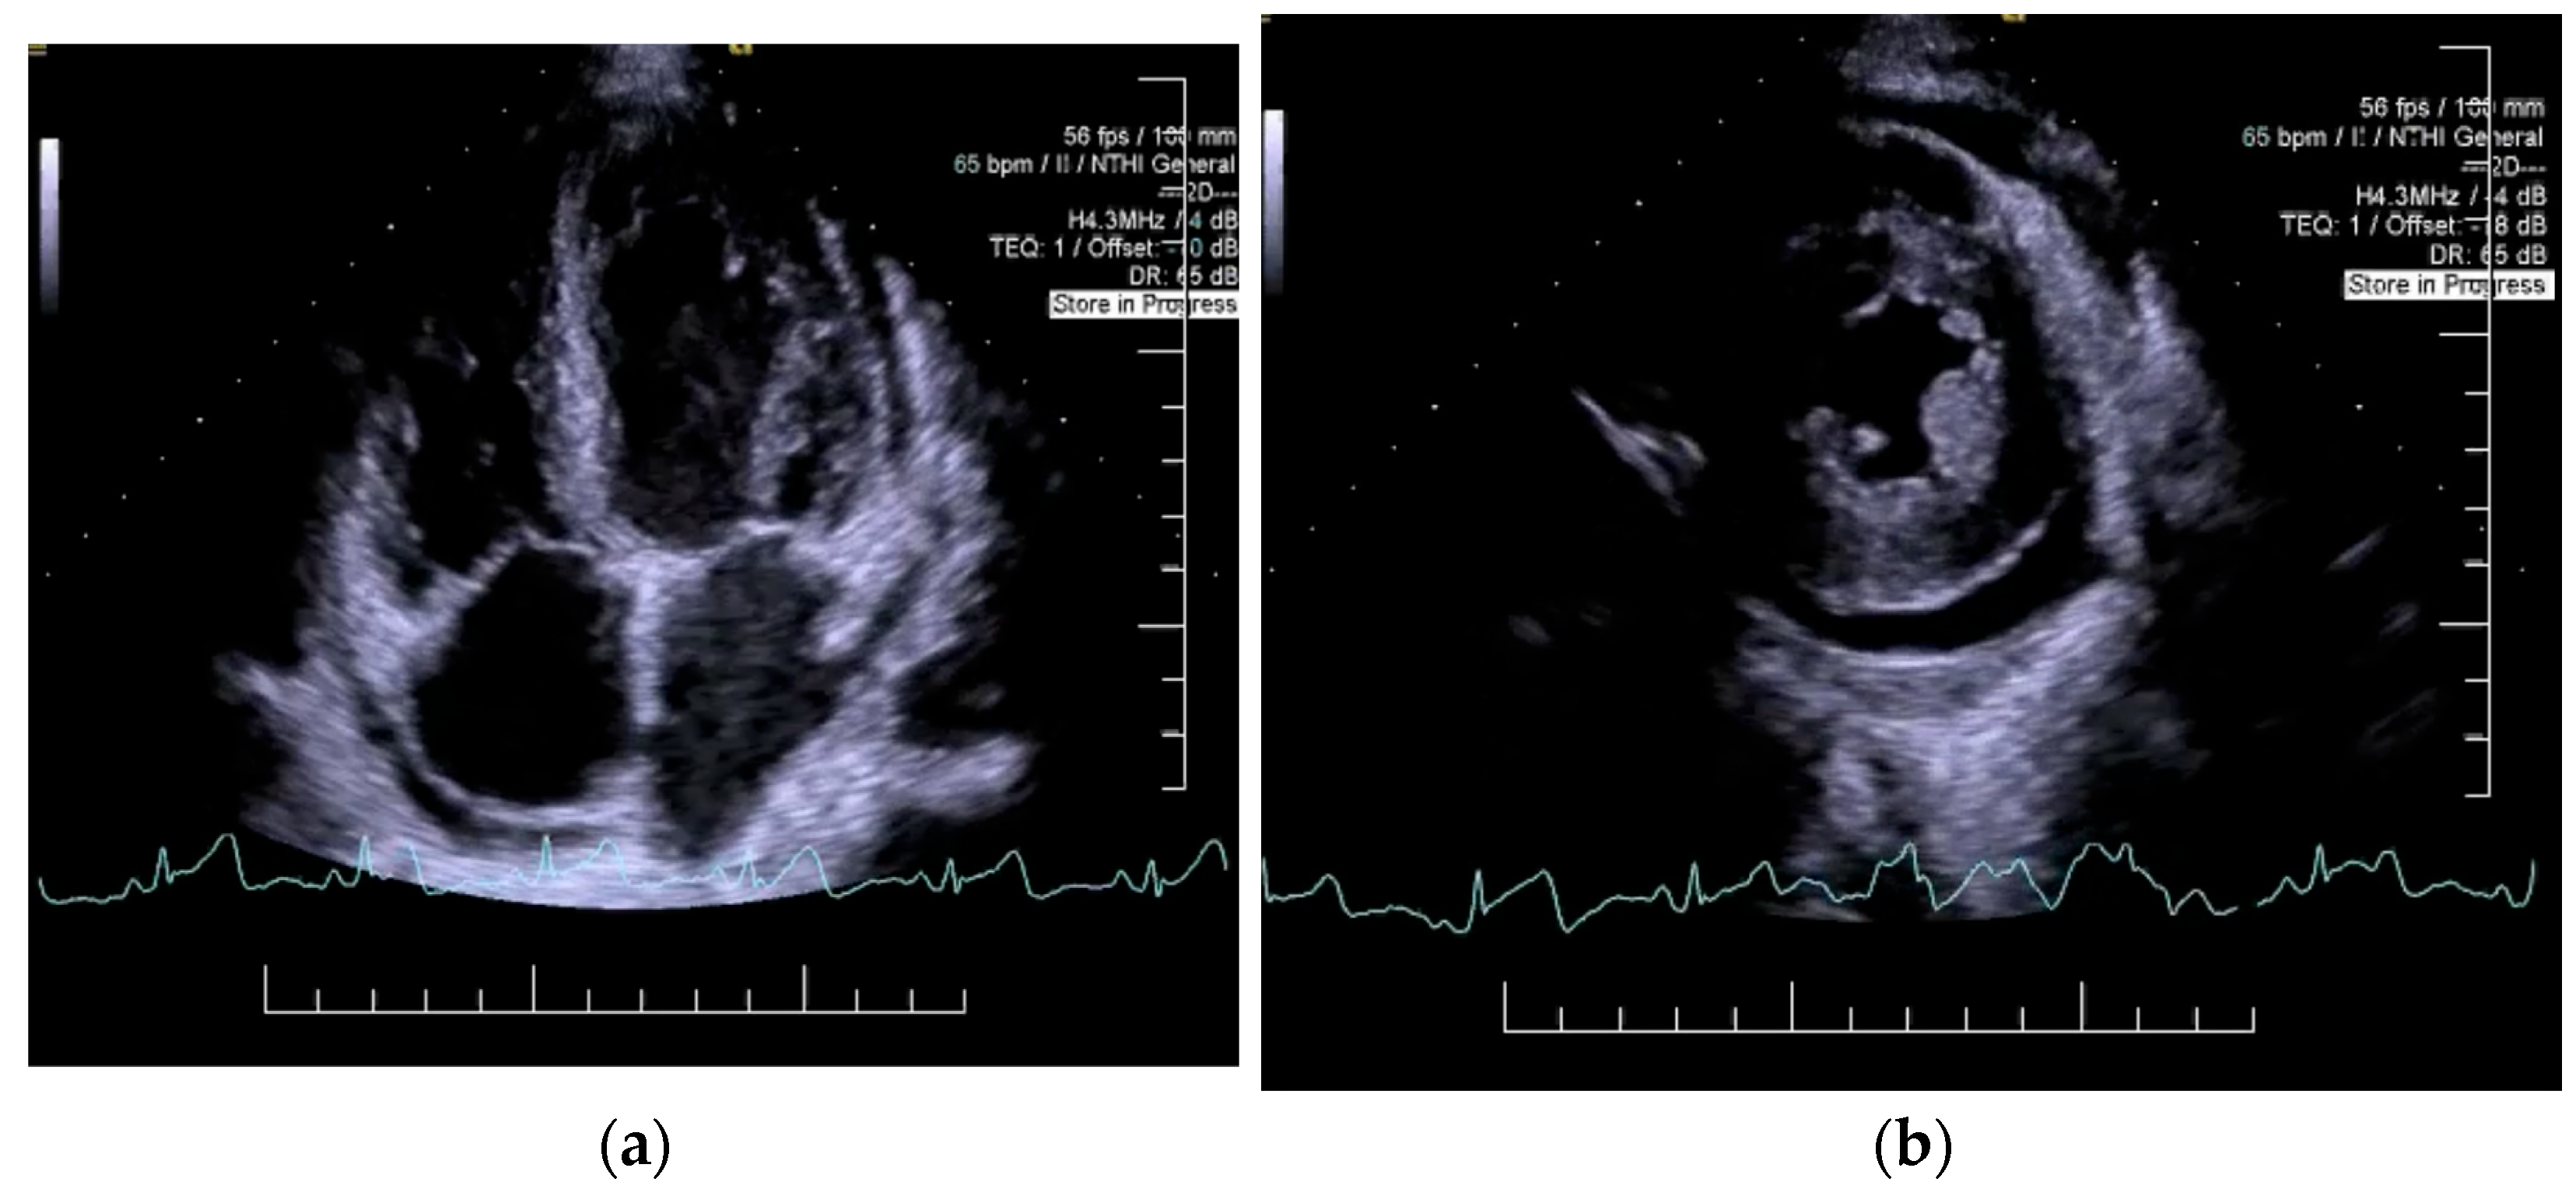

2. Case Presentation